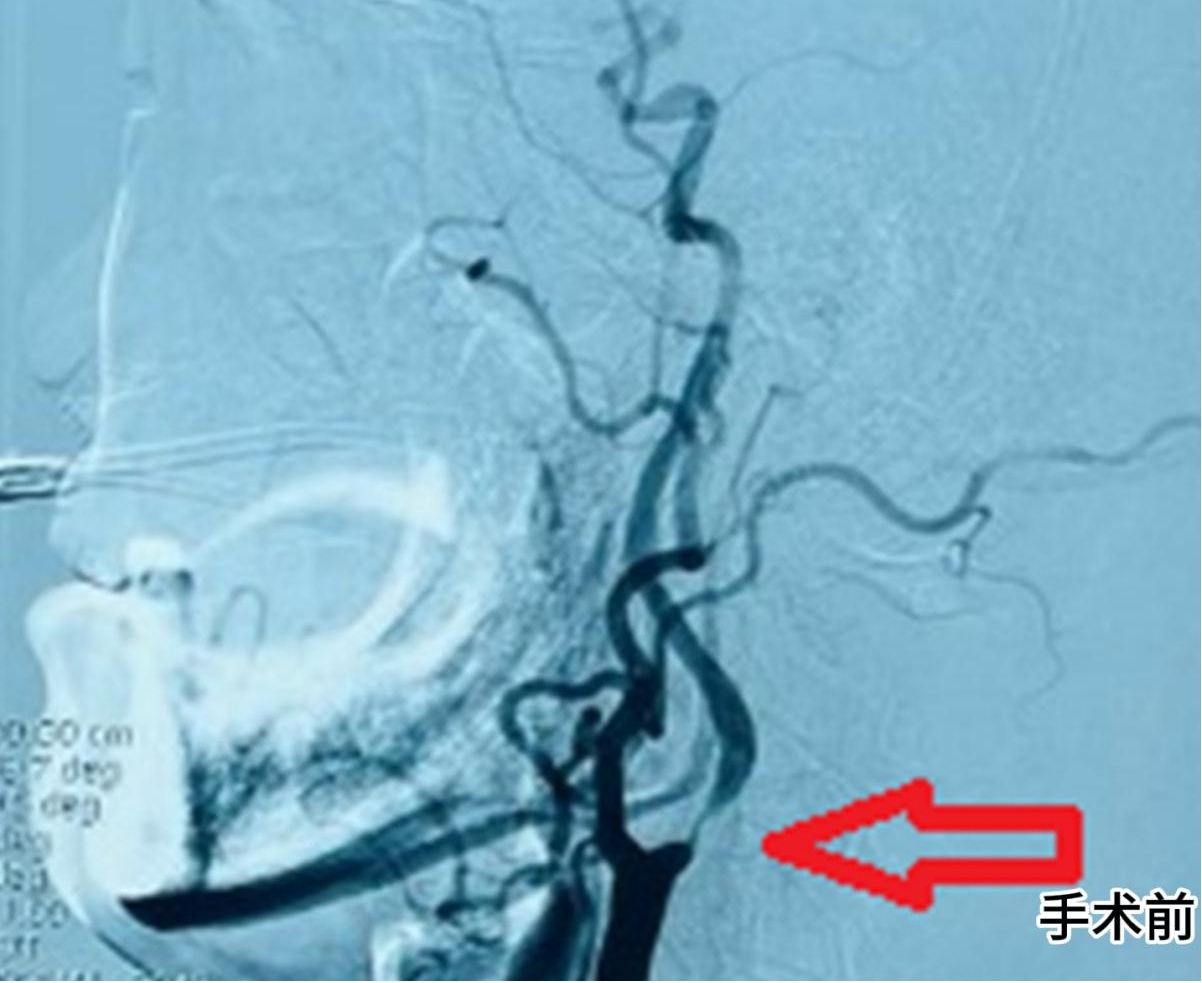

“患者入院时左下肢无力已持续 1 个月,颅脑 MRI 检查显示右侧顶叶存在急性 - 亚急性期梗塞灶,而颈部血管超声和 CTA 的结果更令人揪心。” 神经内科(介入)副主任司君增博士回忆道。检查数据显示,大爷右颈内动脉起始部狭窄程度高达 90-99%,残余内径仅 0.5mm,相当于血管几乎完全闭塞。

手术由司君增副主任医师主刀,在局麻状态下,团队通过股动脉穿刺建立微小通路,将介入器械精准送达狭窄部位。“老年患者血管往往存在迂曲钙化,器械推送难度极大,我们借助高清血管造影系统实时导航,确保支架定位误差不超过 1 毫米。” 司君增介绍。整个手术历时 40 分钟,术后即刻造影显示,大爷闭塞的颈动脉完全再通,血流恢复正常。